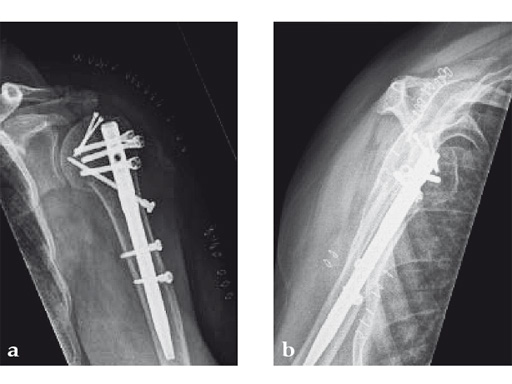

The patient was operated on in beach chair position. For the exploration of the radial nerve, a limited anterolateral approach was used. The nerve was mobilized and retracted laterally. An anterolateral approach to the proximal humerus was performed. The supraspinatus showed a small acute rupture without retraction. The supraspinatus tendon was split to get access to the insertion area on the humeral head. A 270 mm long MultiLoc Humeral Nail of 8.5 mm diameter was inserted under visual and x-ray control to the desired endpoint. Reduction of both the proximal and the distal humerus fracture was anatomical. In the lateral view there was a small gap, and it was decided to apply compression after distal locking (Fig 12). Proximally, three MultiLoc screws were inserted and a 2 mm end cap was placed. Finally, the supraspinatus rupture was reconstructed with transosseous sutures and secured with an augmentation plate. The posterior greater tuberosity fracture was secured with Fiber Wire to the MultiLoc screws. Fig 13 illustrates the definitive fixation.

Postoperatively, no sling was used because the patient stayed in medically induced coma.